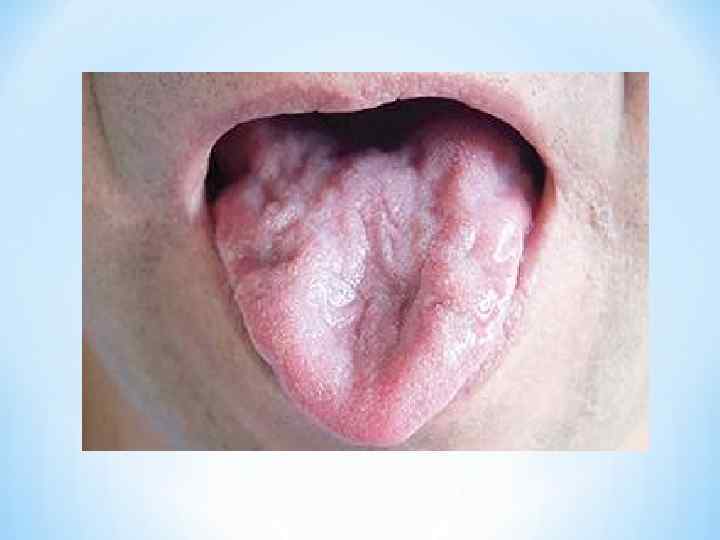

* Для БАС в большинстве случаев характерна асимметричность * симптоматики. * В атрофированных обнаруживаются фасцикуляции(локальные или распространенные) * В типичном случае начало заболевания с похудания мышц тенара одной из кистей с развитием слабости аддукции (приведения) и оппозиции большого пальца, (обычно асимметрично), что затрудняет схватывание большим и указательным пальцами и приводит к нарушениям тонкого моторного контроля в мышцах кисти. Больной ощущает затруднения при подбирании мелких предметов, при застегивании пуговиц, при письме. * Затем, в процесс вовлекаются мышцы предплечья, а кисть приобретает вид «когтистой лапы» . Через несколько месяцев развивается сходное поражение другой руки. Атрофия, постепенно распространяясь, захватывает мышцы плеча и плечевого пояса. * Одновременно с этим или позже часто развивается поражение бульбарных мышц: фасцикуляции и атрофия языка, парез мягкого неба, атрофия мышц гортани и глотки, что проявляется в виде дизартрии (нарушения речи), дисфагии (нарушения глотания), слюнотечения. Мимические и жевательные мышцы обычно поражаются позже других групп мышц. По мере развития заболевания становится невозможным высовывание языка, надувание щек, вытягивание губ в трубочку. Иногда развивается слабость разгибателей головы, из за чего больной не может держать голову прямо. При вовлечении в процесс диафрагмы наблюдается парадоксальное дыхание (на вдохе живот западает, на выдохе выпячивается).

* Для БАС в большинстве случаев характерна асимметричность * симптоматики. * В атрофированных обнаруживаются фасцикуляции(локальные или распространенные) * В типичном случае начало заболевания с похудания мышц тенара одной из кистей с развитием слабости аддукции (приведения) и оппозиции большого пальца, (обычно асимметрично), что затрудняет схватывание большим и указательным пальцами и приводит к нарушениям тонкого моторного контроля в мышцах кисти. Больной ощущает затруднения при подбирании мелких предметов, при застегивании пуговиц, при письме. * Затем, в процесс вовлекаются мышцы предплечья, а кисть приобретает вид «когтистой лапы» . Через несколько месяцев развивается сходное поражение другой руки. Атрофия, постепенно распространяясь, захватывает мышцы плеча и плечевого пояса. * Одновременно с этим или позже часто развивается поражение бульбарных мышц: фасцикуляции и атрофия языка, парез мягкого неба, атрофия мышц гортани и глотки, что проявляется в виде дизартрии (нарушения речи), дисфагии (нарушения глотания), слюнотечения. Мимические и жевательные мышцы обычно поражаются позже других групп мышц. По мере развития заболевания становится невозможным высовывание языка, надувание щек, вытягивание губ в трубочку. Иногда развивается слабость разгибателей головы, из за чего больной не может держать голову прямо. При вовлечении в процесс диафрагмы наблюдается парадоксальное дыхание (на вдохе живот западает, на выдохе выпячивается).

*Клиника основных форм заболевания: * Шейно-грудная форма (50% случаев). Характерны атрофические и спастико- атрофические парезы рук и спастические парезы ног. * Бульбарная форма (25% случаев). Преобладают бульбарные нарушения (паралич мягкого неба, языка, слабость жевательных мышц, нарушения речи, глотания, непрерывное истечение слюны, на поздних стадиях дыхательные расстройства), возможно присоединение псевдобульбарных проявлений в виде насильственного смеха и плача, оживления нижнечелюстного рефлекса. Позднее присоединяются признаки поражения конечностей. При этой форме самая короткая продолжительность жизни: больные умирают от бульбарных нарушений (вследствие аспирационной пневмонии, дыхательной недостаточности), при этом нередко оставаясь способны к самостоятельному передвижению. * Пояснично-крестцовая форма (20 – 25% случаев). Развиваются атрофические парезы ног при нерезко выраженных пирамидных симптомах. На поздних этапах вовлекаются мышцы рук и краниальная мускулатура. * Высокая (церебральная) форма (1 – 2%). Проявляется спастическим тетрапарезом (или нижним парапарезом), псевдобульбарным синдромом (насильственный смех и плач, оживление нижнечелюстного рефлекса) при минимальных признаках поражения периферических мотонейронов. *

*Клиника основных форм заболевания: * Шейно-грудная форма (50% случаев). Характерны атрофические и спастико- атрофические парезы рук и спастические парезы ног. * Бульбарная форма (25% случаев). Преобладают бульбарные нарушения (паралич мягкого неба, языка, слабость жевательных мышц, нарушения речи, глотания, непрерывное истечение слюны, на поздних стадиях дыхательные расстройства), возможно присоединение псевдобульбарных проявлений в виде насильственного смеха и плача, оживления нижнечелюстного рефлекса. Позднее присоединяются признаки поражения конечностей. При этой форме самая короткая продолжительность жизни: больные умирают от бульбарных нарушений (вследствие аспирационной пневмонии, дыхательной недостаточности), при этом нередко оставаясь способны к самостоятельному передвижению. * Пояснично-крестцовая форма (20 – 25% случаев). Развиваются атрофические парезы ног при нерезко выраженных пирамидных симптомах. На поздних этапах вовлекаются мышцы рук и краниальная мускулатура. * Высокая (церебральная) форма (1 – 2%). Проявляется спастическим тетрапарезом (или нижним парапарезом), псевдобульбарным синдромом (насильственный смех и плач, оживление нижнечелюстного рефлекса) при минимальных признаках поражения периферических мотонейронов. *